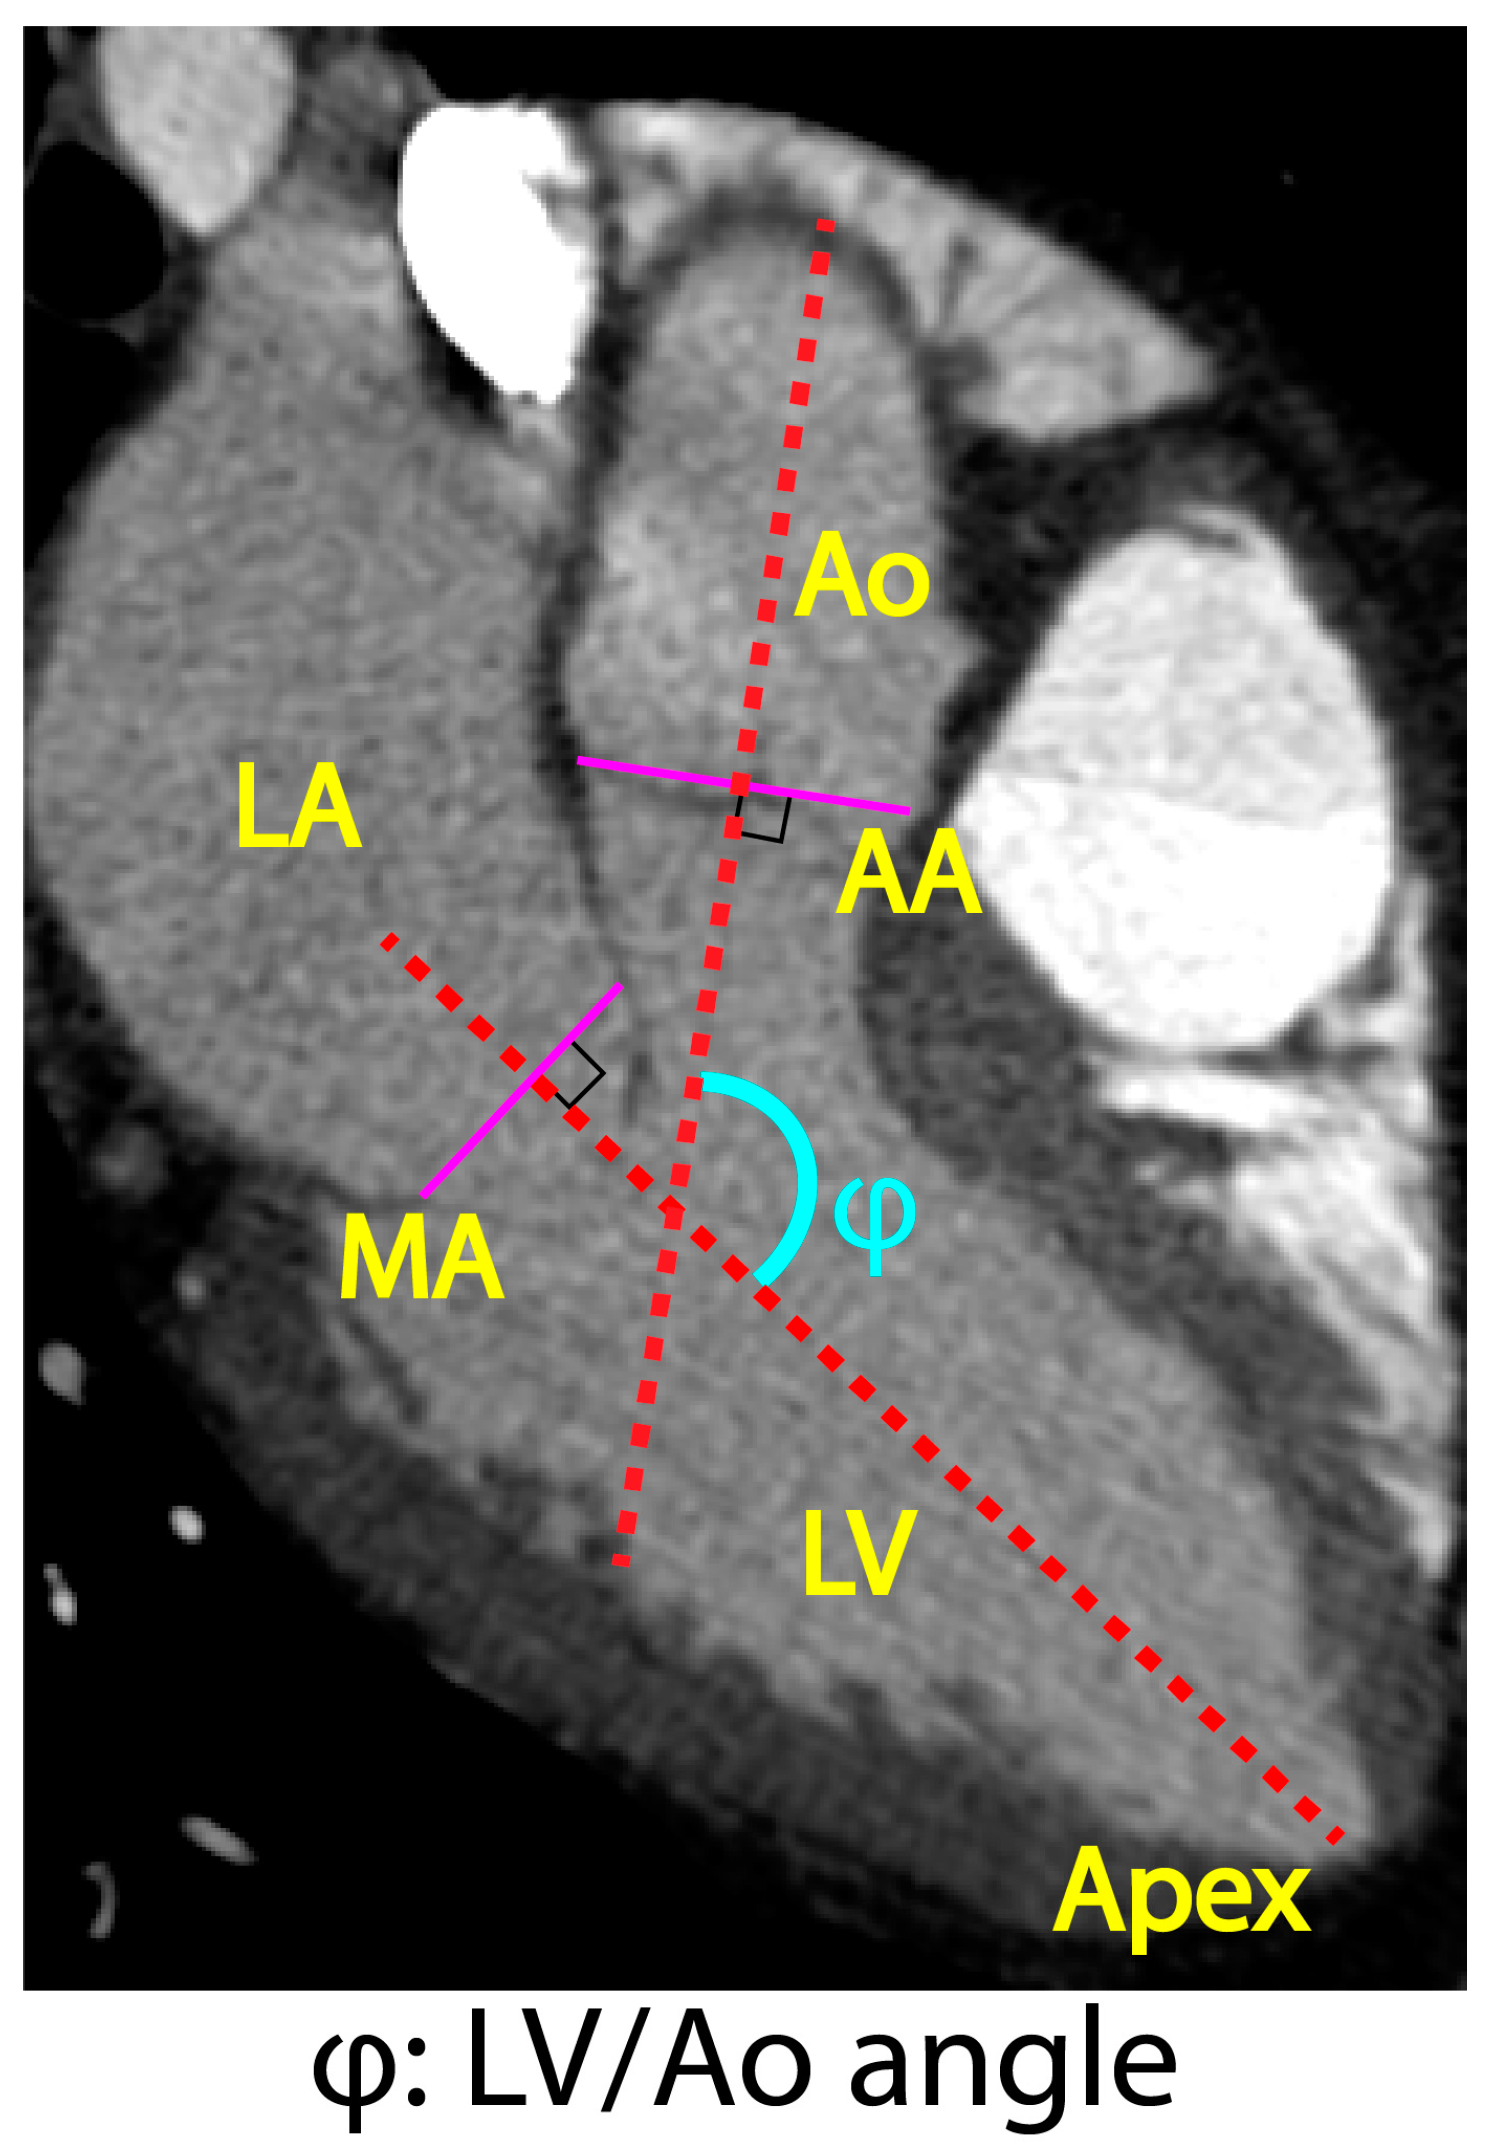

2.3.4. Axial Tilt and Aortic Rotation

- Kwon, D.H.; Smedira, N.G.; Popovic, Z.B.; Lytle, B.W.; Setser, R.; Thamilarasan, M.; Schoenhagen, P.; Flamm, S.D.; Lever, H.M.; Desai, M.Y. Steep left ventricle to aortic root angle and hypertrophic obstructive cardiomyopathy: Study of a novel association using three-dimensional multimodality imaging. Heart 2009, 95, 1784–1791. [Google Scholar] [CrossRef]

| LV/Ao angle (degrees) | 132.5 ± 9.5 | 134.4 ± 6.4 | 134.9 ± 7.4 | 126.4 ± 6.4 | <0.01 |